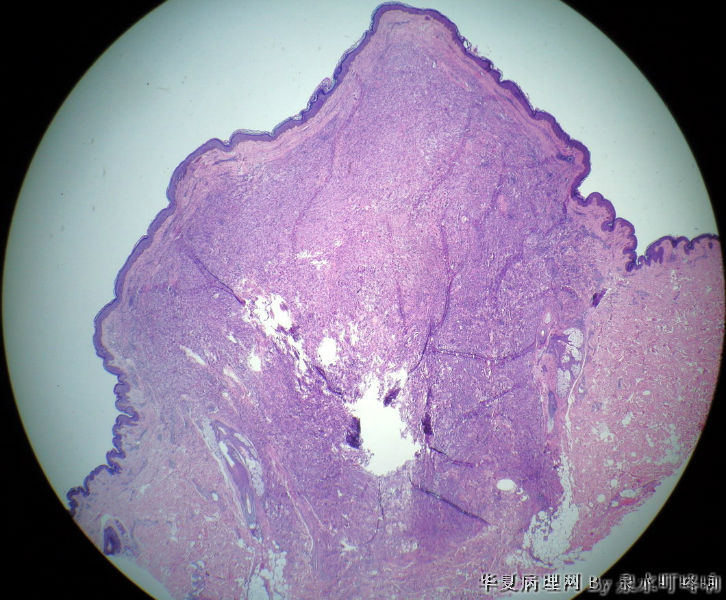

颈后部肿物

• 颈后部肿物图1

图1

女,39岁,颈后部肿物半年。

大体:灰白皮表肿物一个,呈半球形,直径0.9厘米,高出皮表0.9厘米,切面灰白,质中。